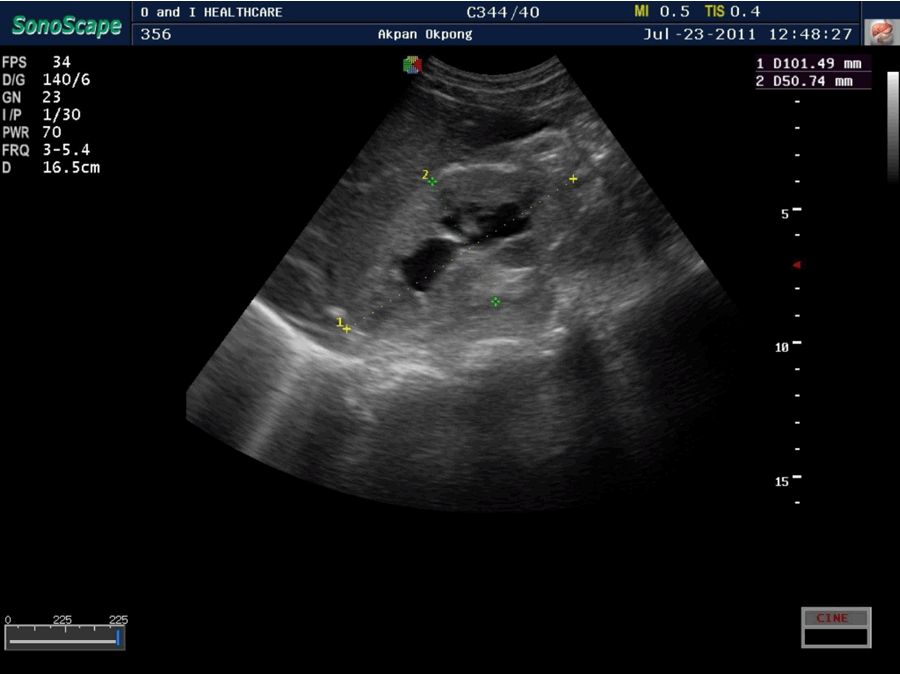

Clinical examination showed a weak, elderly man, with low body temperature (35°C), a respiratory rate of 30/min and an obtunded sensorium. There was bilateral pitting pedal oedema, generalized lower abdominal tenderness and the bladder size was 24 weeks. Abdomino-pelvic and transrectal ultrasonographic examination showed uniformly enlarged prostate (prostatic volume 85 cc) with no calcifications or suspicious foci, an enlarged bladder containing an estimated 1000 mL of fluid with fluid-fluid level, bilateral hydronephrosis and grade 3 renal parenchymal disease (Figures 1 and 2).

Figure 2: Ultrasound scan showed kidney with hydronephrosis and Grade 3 paranchymal disease.